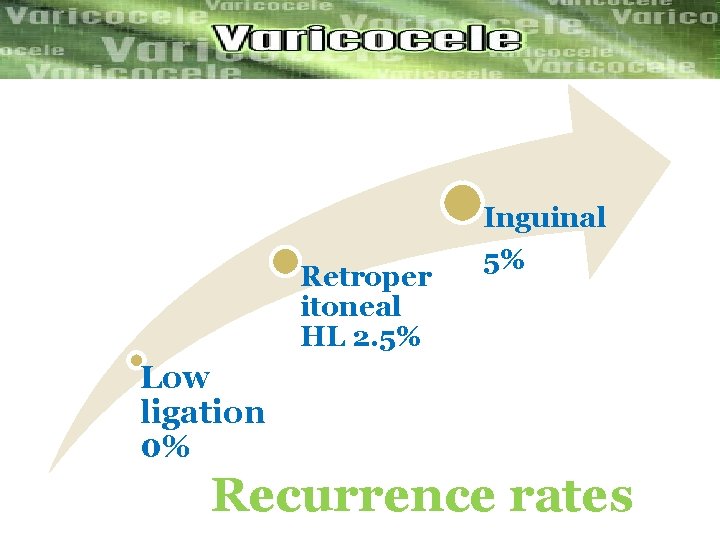

Recurrence rate 6. 00 % 5. 00 % 4. 00 % Recurrance 3. 00 % 2. 00 % 1. 00 % 0. 0 0% Inguinal Retroperitoneal Hl Recurrence rates inguinal 5% (2 cases) Retroperitoneal HL 2. 5% (1 case) Low ligation LL (none case) Low Ligation

Inguinal Retroper itoneal HL 2. 5% 5% Low ligation 0% Recurrence rates

Conclusion Ø As a microsurgical approach to the treatment Of varicocele , low ligation is better than inguinal High ligation and retroperitoneal high ligation in improving Recurrence rate and seminal parameters of the patients.